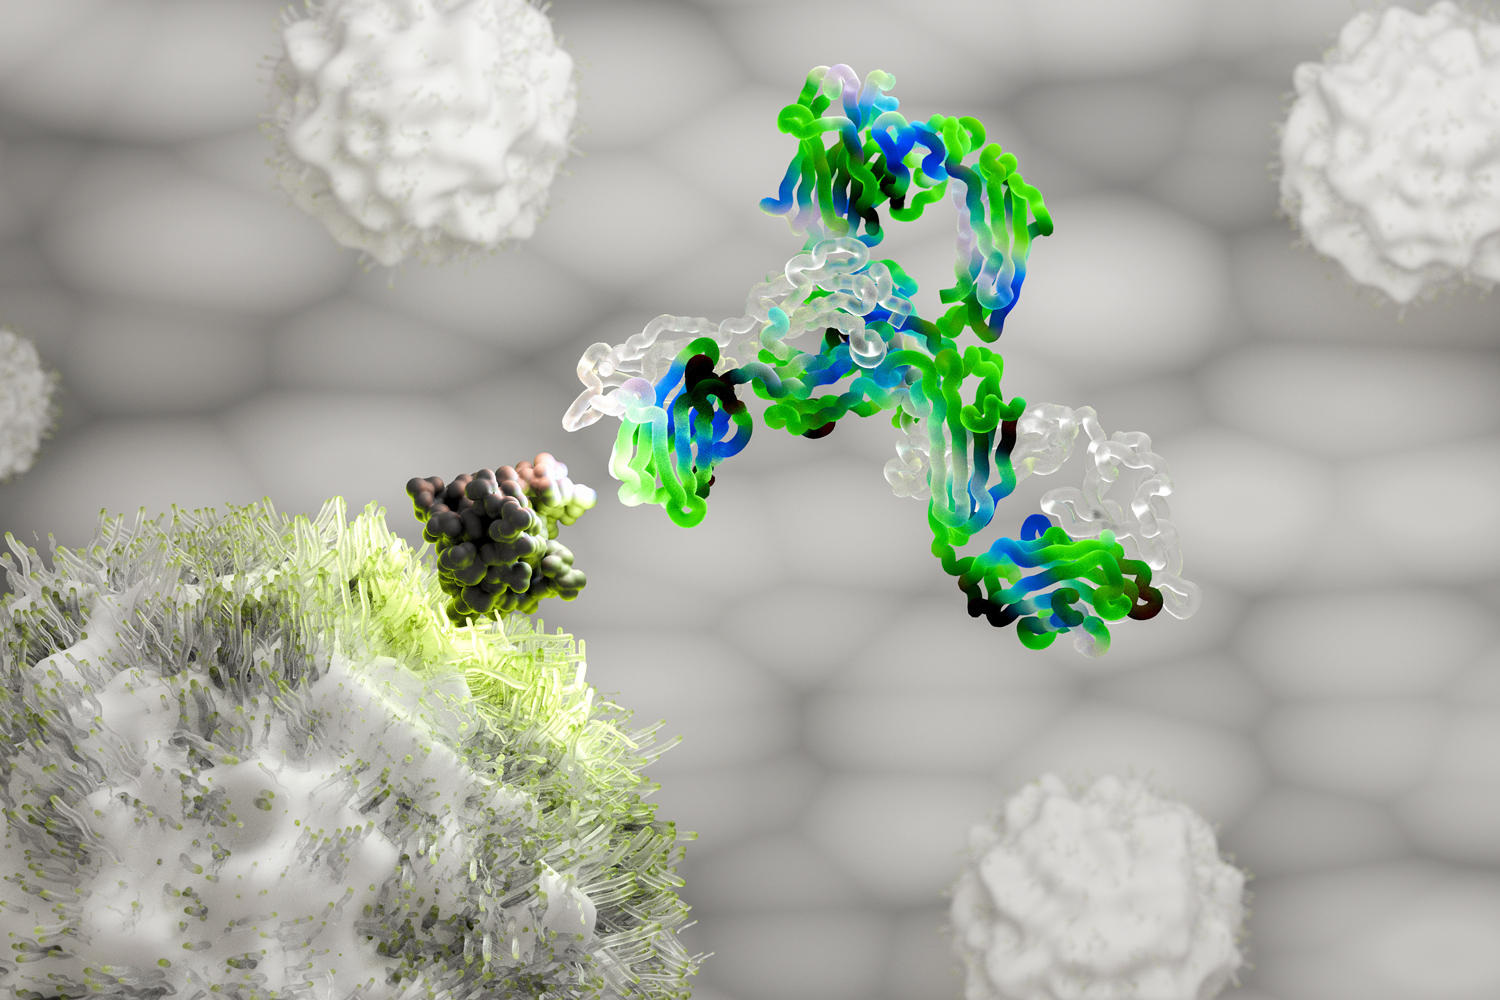

To Discover